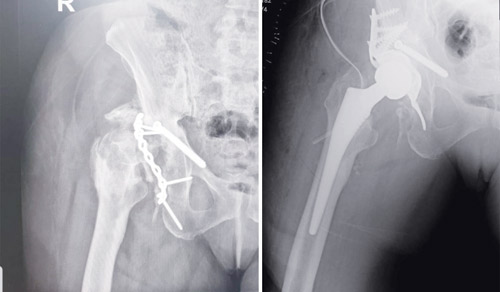

وأضاف د. حمدان أن السيدة تعرضت لحادث سير منذ 4 سنوات أصيبت على إثره بكسور في الجزء الأيمن بمنطقة الورك مما سبب لها خلع المفصل، وعند محاولة علاجه جراحياً في ذلك الوقت لم تنجح عملية تثبيت الكسور والتئامها، ومع مرور الوقت أدى ذلك إلى تكرار خلع مفصل الورك وحدوث تيبّس كامل، والإصابة بتكلسات شديدة حول المفصل (Hetertropic Ossification)، كما تبين من الفحوصات أيضاً وجود قصر في الطرف السفلي الأيمن.

وقال الدكتور علاء إن الفريق الطبي قرر التدخل الجراحي مشيراً إلى أن العملية الجراحية استغرقت 4 ساعات تم فيها إزالة التكلسات للمساعدة في تحريك المفصل، ومن ثم تحرير العضلات القصيرة لزيادة الحركة، كما تم إزالة المعدن المتخلخل من العملية السابقة وزراعة طعم عظمي، تبع ذلك زراعة مفصل صناعي للورك.

وأكد الدكتور علاء حمدان أن جهود الفريق الطبي تكللت بالنجاح ولله الحمد، حيث تم إرجاع حركة المفصل بشكل ممتاز، بالإضافة إلى استعادة طول الطرف السفلي الأيمن إلى طبيعته، مع البدء المباشر في اتباع برنامج علاج طبيعي أثناء مرحلة التنويم، وقد استطاعت المريضة المشي منذ اليوم الثاني للعملية، وخرجت إلى منزلها في اليوم السابع وهي بصحة جيدة.